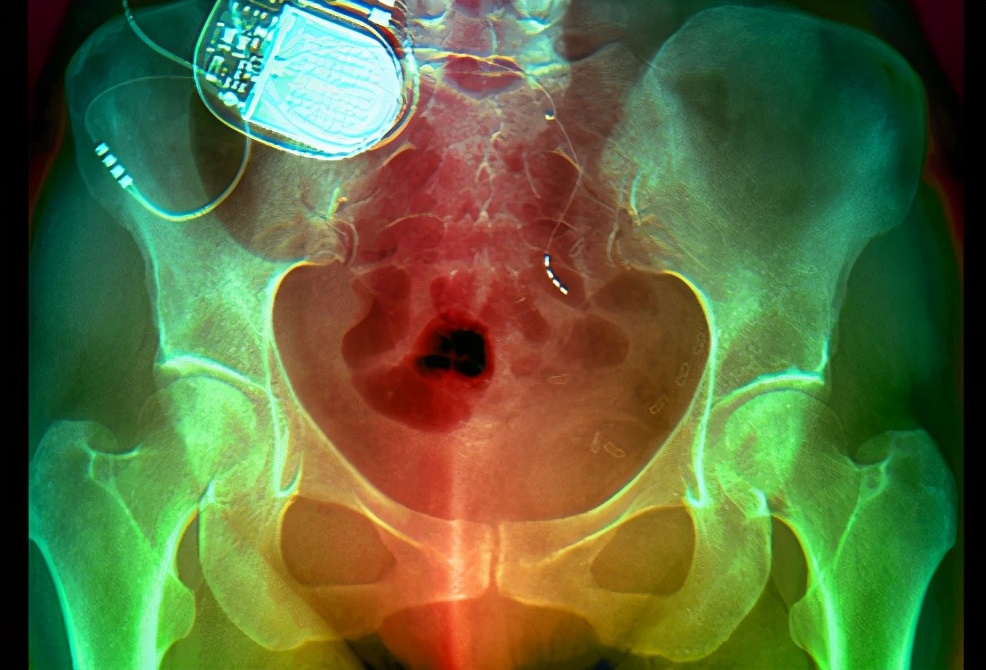

- 电刺激装置,可用电刺激膀胱周围的神经、控制痉挛,以改善急迫性尿*禁失**;